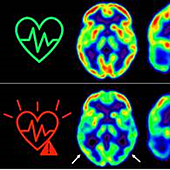

El Covid-19 puede aumentar el riesgo de diabetes de tipo 1 en niños

La diabetes tipo 1 se produce cuando el propio sistema inmunológico del cuerpo ataca a las células del páncreas que producen insulina, que regula los niveles de azúcar en sangre. Como resultado, los niveles de azúcar en sangre pueden oscilar peligrosamente. A largo plazo, esto puede dañar los vasos sanguíneos de las personas, lo que a su vez puede provocar ceguera, insuficiencia renal, ataques cardíacos o daños a los nervios que, en el peor de los casos, requieren la amputación de una extremidad.